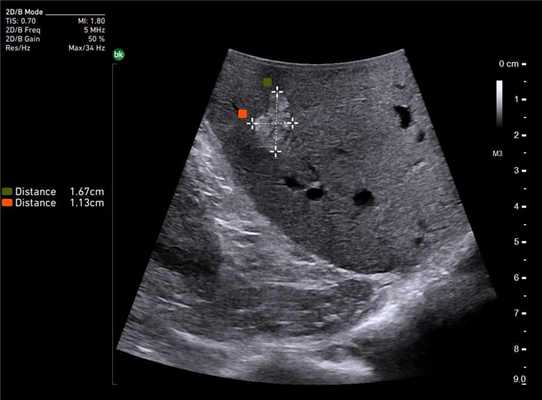

Клинический пример N2. Пациентка Р. находилась на лечении в ГУРОНЦ РАМН. При прохождении обследования был установлен диагноз рак толстой кишки. По данным ультразвуковой компьютерной томографии на фоне выраженной диффузной неоднородности паренхимы печени очаговые образования не определялись. При проведении ангиографии и компьютерной томографии так же убедительных данных за наличие метастазов в печень получено не было. При интраоперационном ультразвуковом исследовании были выявлены два очага, характерными особенностями которых являлись малые размеры (0,2 - 0,4 см), а так же нечеткость контуров и изоэхогенность структуры (рис. 1 а,б).

Рис. 1. Метастатические очаги (стрелки) в печени при интраоперационной ультразвуковой томографии.